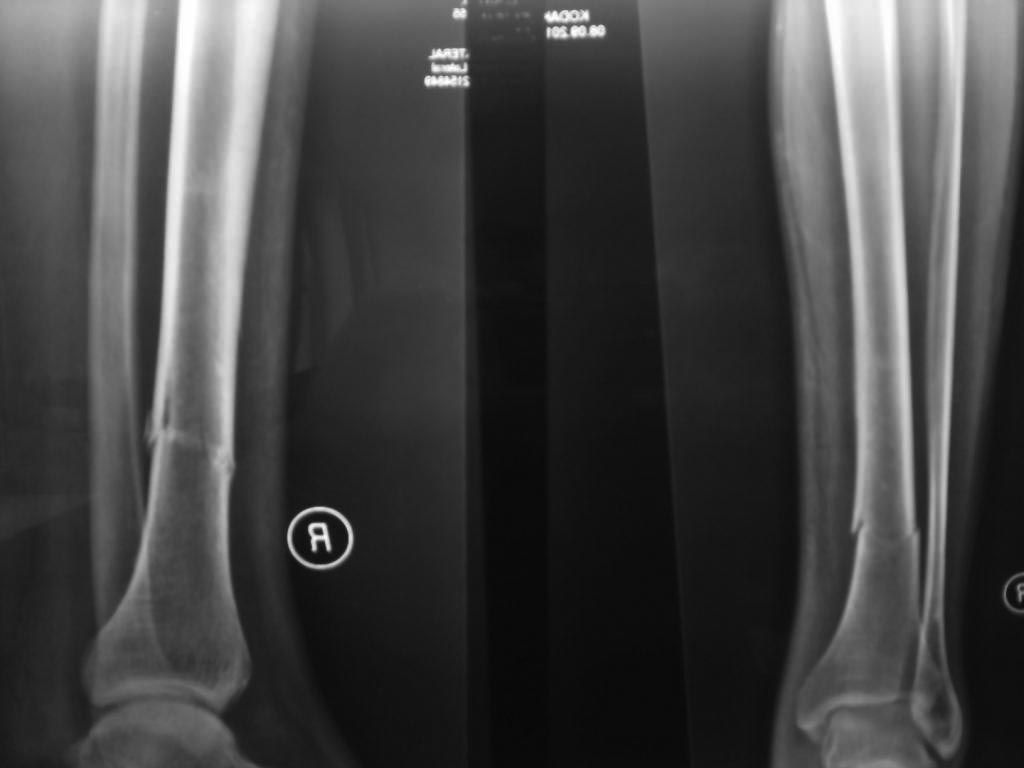

Ув.коллеги Поступил больной, 40 лет, получил перелом нижней трети б/б кости без травмы (оступился). Перед этим отмечал периодические боли в ноге на протяжении месяца. Больному диагностировали синдром Фабри израильские коллеги где-то год назад.

Вопрос: встречался ли кто с подобным, тактика лечения (думаем заштифтовать и/м стержнем) и каковы возможные ортопедические осложнения? Спасибо С уважением, Тарас Рокита больница №7, Киев

Остеопороз с возможностью патологических переломов одно из характерных проявлений болезни Фабри. В принципе, существует заместительная энзимная терапия, но она очень дорога и малодоступна. А стандартное лечение остеопороза должно сопутствовать хирургическому лечению перелома. Поскольку еще одним возможным проявлением болезни являются остеонекрозы, в том числе, дистального конца большеберцовой кости, желательно выполнить КТ голени. И денситометрию, само собой.